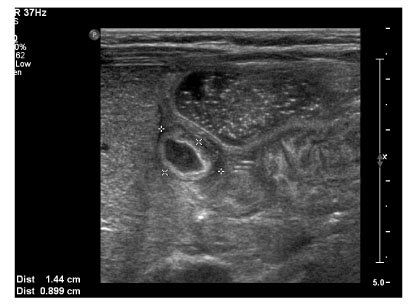

Fig. 2

Postnatal ultrasonogram at 4 weeks after birth showing hypoechoic mass (1.4 × 0.9 cm) with thickened wall at the stomach

Fig. 2 Postnatal ultrasonogram at 4 weeks after birth showing hypoechoic mass (1.4 × 0.9 cm) with thickened wall at the stomach